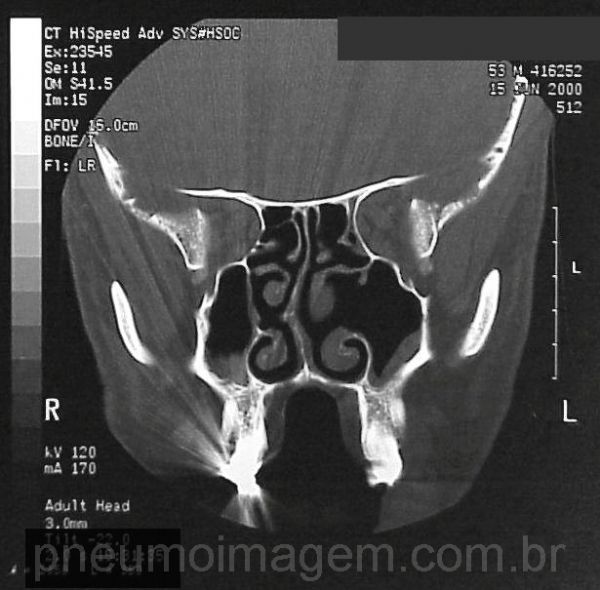

Radiografia dos seios da face com desvio do septo e espessamento de revestimento dos seios maxilares (sinusopatia).

sinusitis.